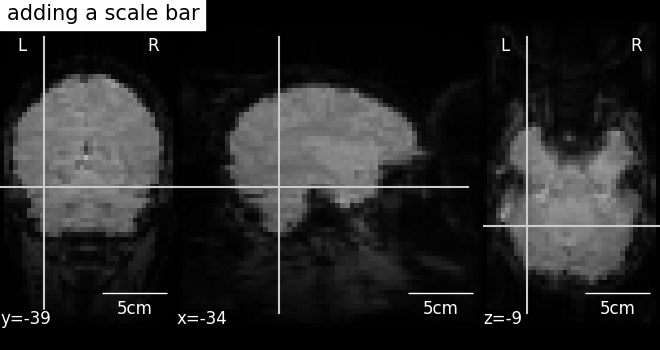

7.4. Adding overlays, edges, contours, contour fillings, markers, scale bar¶

To add overlays, contours, or edges, use the return value of the plotting

functions. Indeed, these return a display object, such as the

nilearn.plotting.displays.OrthoSlicer. This object represents the

plot, and has methods to add overlays, contours or edge maps:

display = plotting.plot_epi(...)